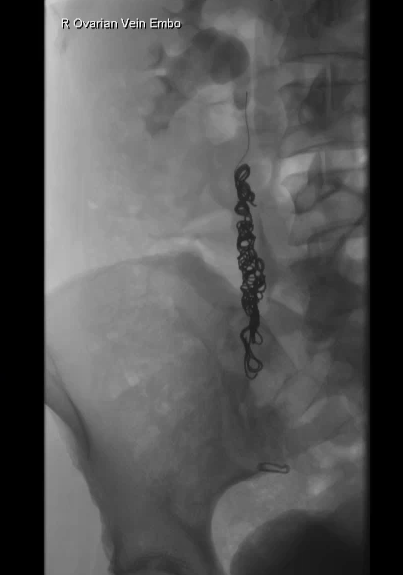

○ Ovarian vein embolisation (OVE) is the most common, where a catheter is inserted into the vein and tiny coils or plugs are placed to block the faulty vein, redirecting blood flow and relieving pressure.

Ovarian Vein Embolisation Procedure

A small catheter is inserted through a vessel in the wrist or groin and guided to the ovarian veins.

Abnormal veins are embolised (blocked) while preserving normal blood flow.